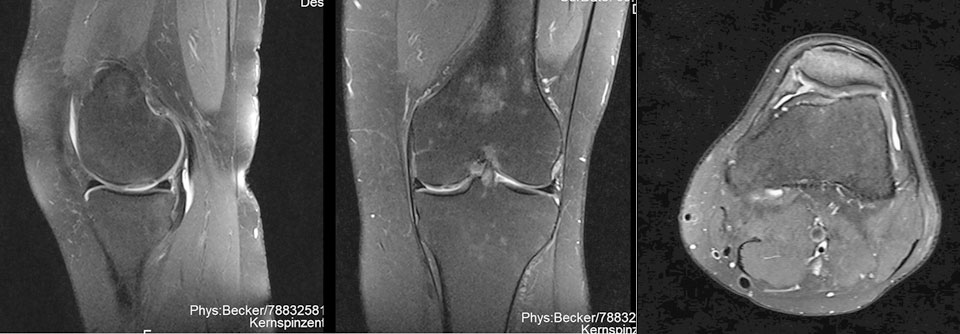

Nach dem Eingriff sind sowohl bei der Dame (links, mitte) als auch beim Surfer (rechts) die Knorpeldefekte komplett gefüllt. Nach dem Eingriff sind sowohl bei der Dame (links, mitte) als auch beim Surfer (rechts) die Knorpeldefekte komplett gefüllt. © Schneider S et al. Hamburger Ärzteblatt 2021; 75: 30-31 © Hamburger Ärzteverlag, Hamburg

Das Verfahren eignet sich laut Dr. Schneider sowohl bei jungen aktiven Sportlern mit Verletzungen als auch für ältere Menschen mit degenerativen Knorpelschäden. Er berichtet über einen 26-Jährigen, der nach Kollision mit einem Surfbrett über Knieschmerzen klagte. Ursache war ein Knorpeldefekt im Bereich der Patella, der erfolgreich mittels Minced-Cartilage-Technik versorgt wurde. Nach zehn Monaten konnte der Mann alle sportlichen Aktivitäten, einschließlich Joggen und Surfen, in vollem Umfang wieder aufnehmen.

Auch eine 64-jährigen Patientin mit einem viertgradigen Knorpelschaden im Bereich der Femurkondylen profitierte von dem Verfahren: Sieben Monate nach dem Eingriff war der Defekt vollständig gefüllt und die ältere Dame konnte ohne Schmerzen wieder Sport treiben.